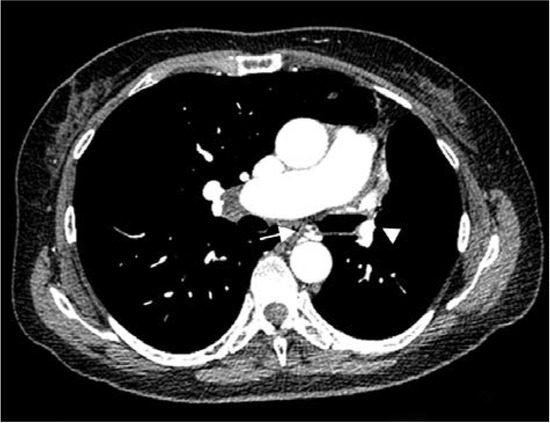

Introduction: Pasteurella multocida colonizes the oropharynx of various domestic and wild animals. In humans, respiratory tract P. multocida infection is the second most frequent localization and usually manifests as pneumonia. Unilateral absence of pulmonary artery (UAPA) is a very rare congenital anomaly. Adult patients with UAPA are usually asymptomatic or their symptoms are nonspecific. Case report: We report a female patient with hemoptysis admitted to our clinic where we isolated P. multocida in sputum. The organism was also isolated from nasopharyngeal swab of her dog. During hospitalization, she was also diagnosed with UAPA and chronic obstructive pulmonary disease (COPD). Discussion: Respiratory P. multocida infection develops more commonly through contact with animal secretions. It occurs most often in immunocompromised patients and in individuals with comorbidities. Hemoptysis very rarely follows P. multocida infection while it is common in cases of UAPA due to existing developed collateral circulation especially in older patients. Conclusions: Ceased hemoptysis after adequate treatment and no recurrence of it over six years of following up the patient led us to conclude that the cause of hemoptysis was P. multocida infection and not UAPA which was more likely to be the case. Full article

Figure 1